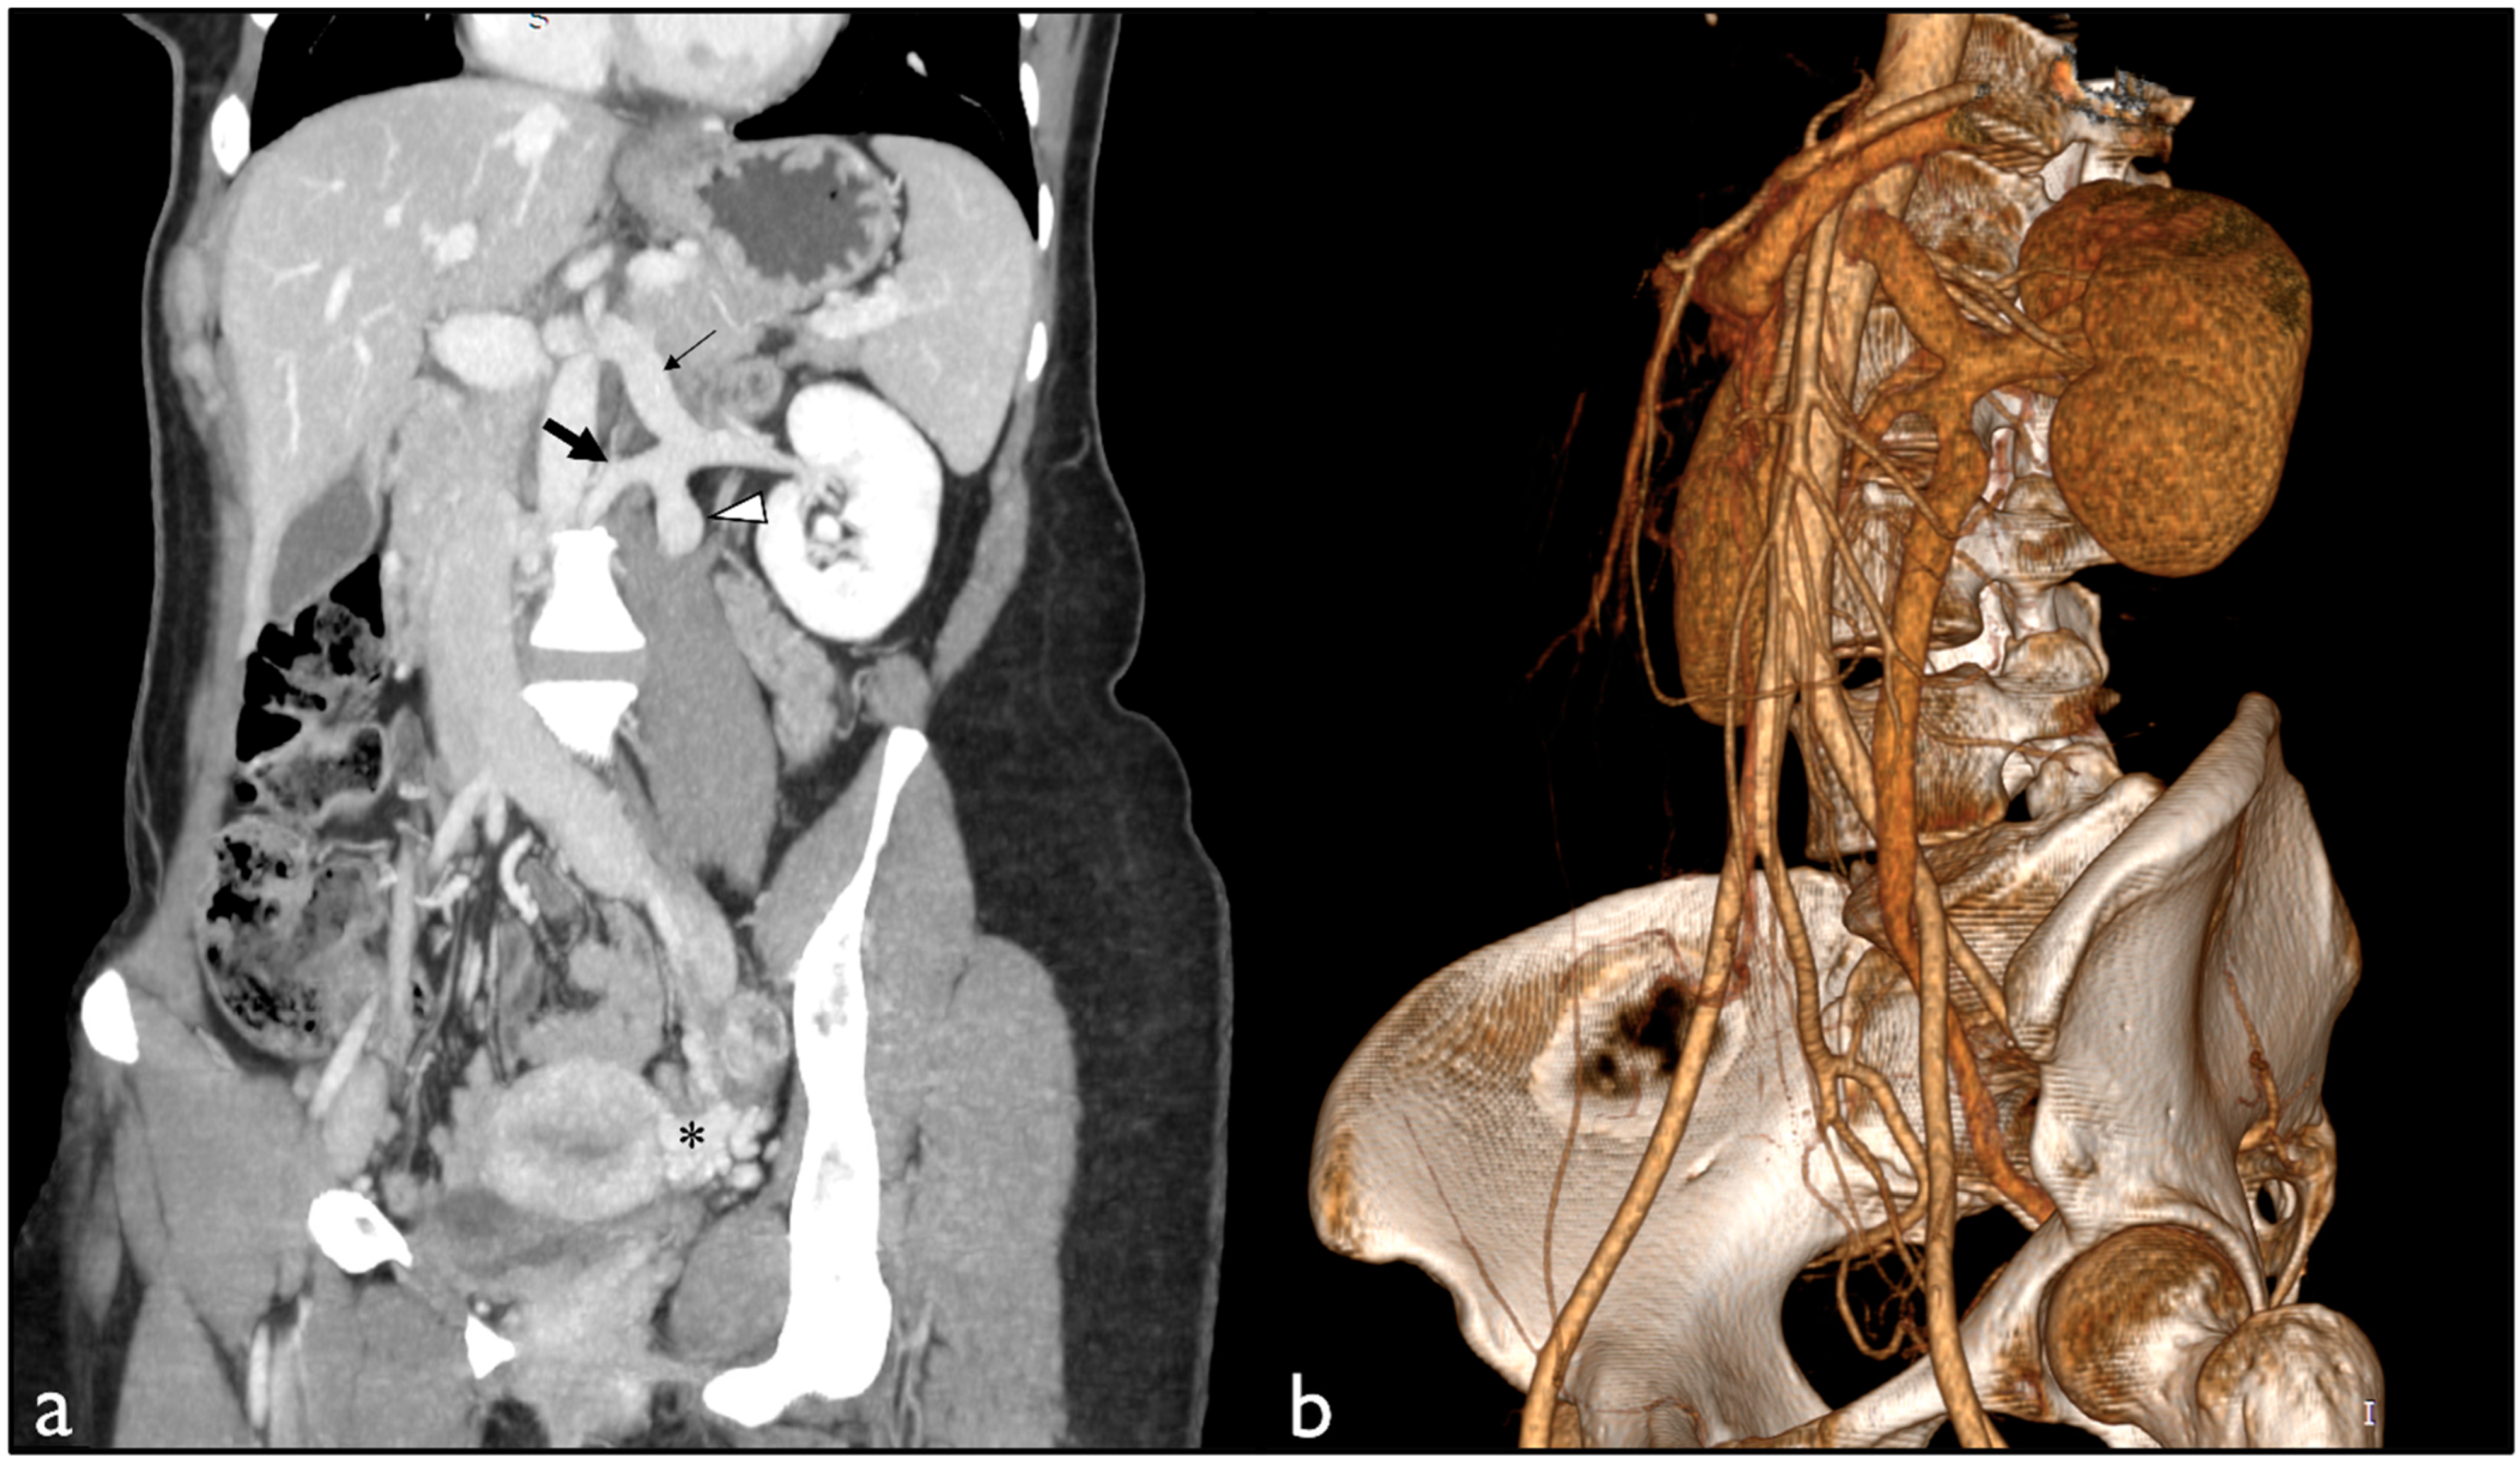

2. Case Presentation